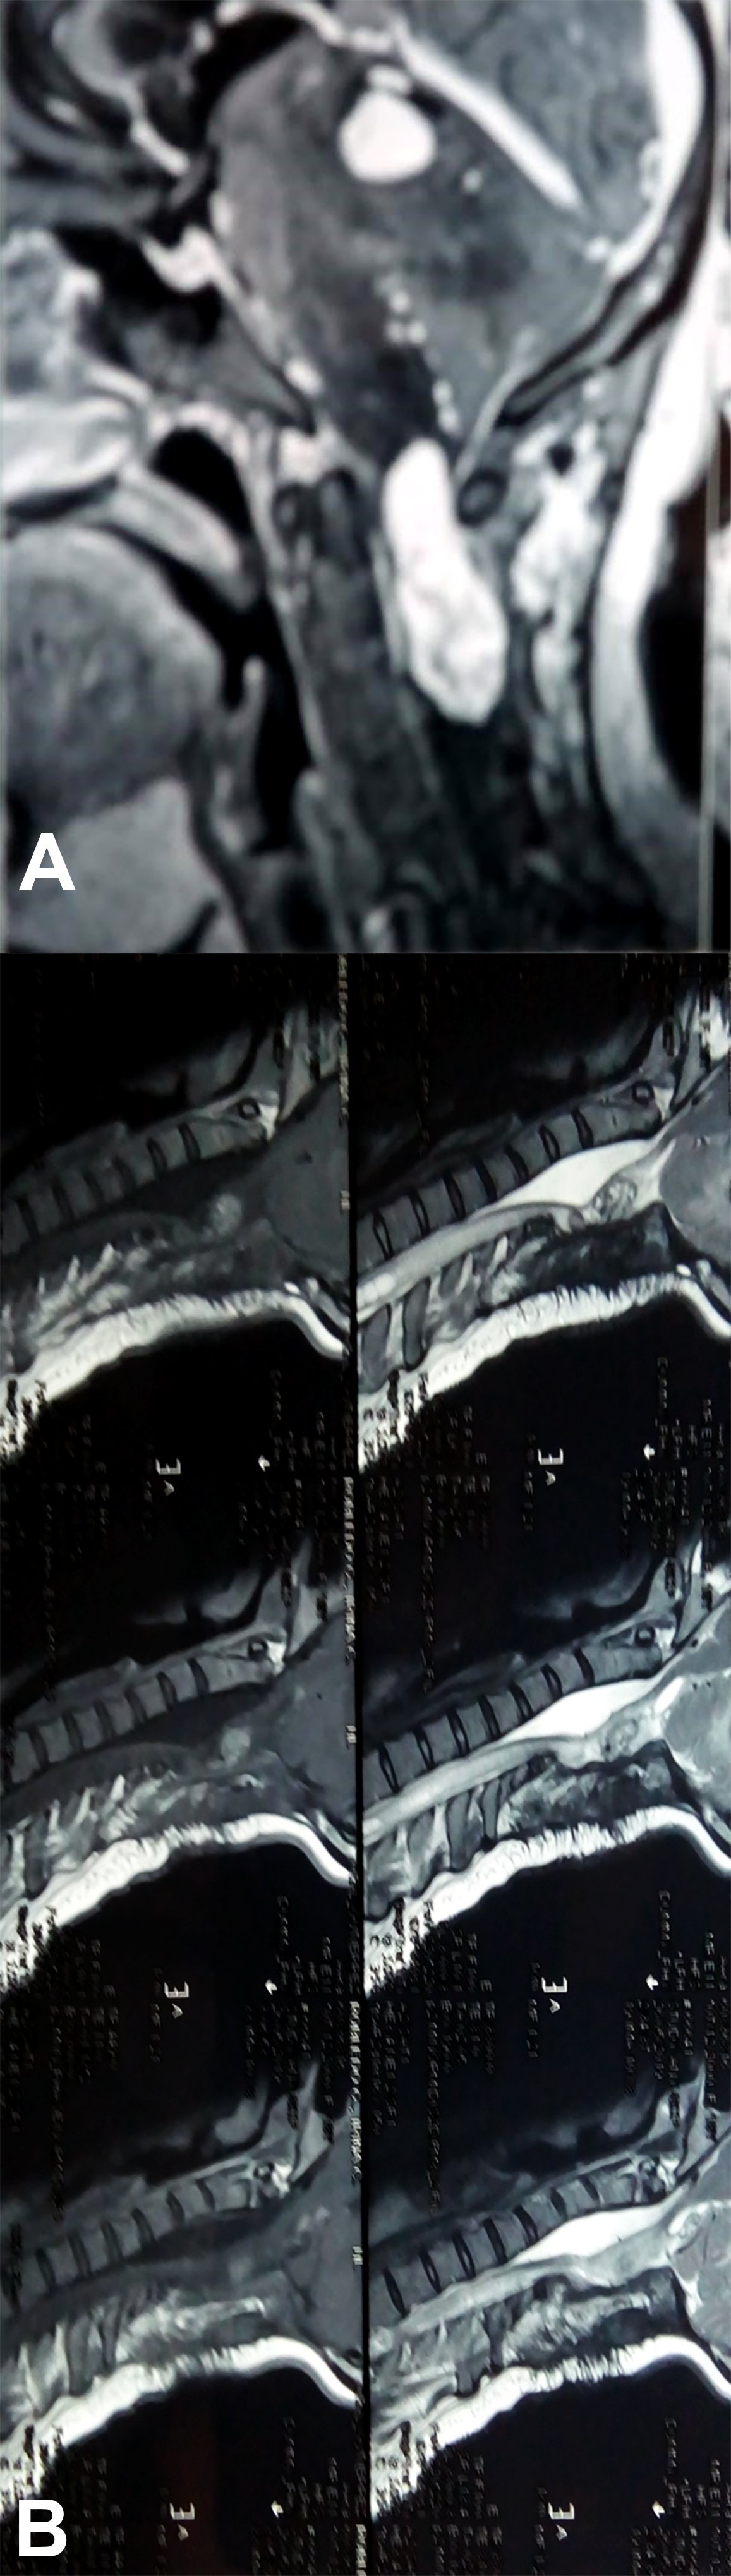

Es evidente que el límite entre el tejido medular y tumoral en las lesiones como los astrocitomas es indiscernible lo que dificulta la posibilidad de resección completa; en los tumores como los ependimomas esta diferencia es más franca y permite seguir un plano de disección seguro (Figuras 3, 4 y 5). Lo anterior condiciona nuestros resultados como han puntualizado diversos autores.5,8 El estado general previo a la cirugía requiere de una valoración juiciosa de las posibilidades de resección. Por ejemplo, el caso 12 (Figura 6) es una paciente portadora de Enfermedad de Von Hippel Lindau, Hemangioblastoma cervical biopsiado en otra institución del exterior del país, fijación de columna cervical y sindrome de Cushing por exceso de medicación corticoidea cuya cirugía debió suspenderse en dos oportunidades por la disminución de su capacidad ventilatoria. Con estos antecedentes y la delgada capa de tejido medular evidenciada intraoperatoriamente se optó por una resección subtotal. A los cuatro meses de la cirugía la paciente recuperó la marcha autónoma y demás parámetros clínicos.

Figura 4: Caso 10. Ependimoma cervical. La línea de puntos delimita la pared de la médula del tumor. Nótese la tinción de hemosiderina en la cara ventral medular.![]()

El caso del Neurocitoma cérvico dorsal (Figura 4), debido a su excepcionalidad, requiere un análisis particular lo cual realizaremos en una comunicación separada.